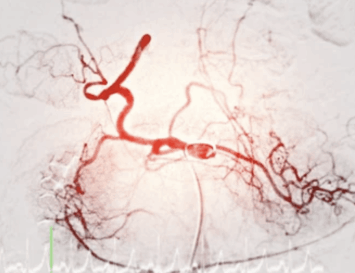

Sistema Endovascular

Dispositivo médico quirúrgico para operaciones vasculares, con varias aplicaciones.